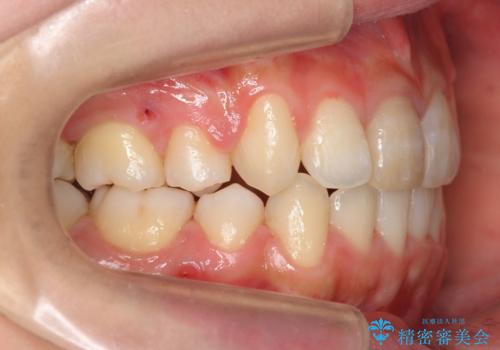

八重歯 前歯のがたがた 抜歯してワイヤー矯正

- 前歯のがたがたを主訴に来院。

八重歯と、前歯のやや開咬の症状もあり難易度としては中等度でした。

上下左右の小臼歯を抜歯し、ワイヤー矯正を行いました。

犬歯のコントロールが難しく、矯正用ミニスクリューを併用しました。

奥歯の歯の間が狭く、ミニスクリューを入れるのも難しい症例でした。